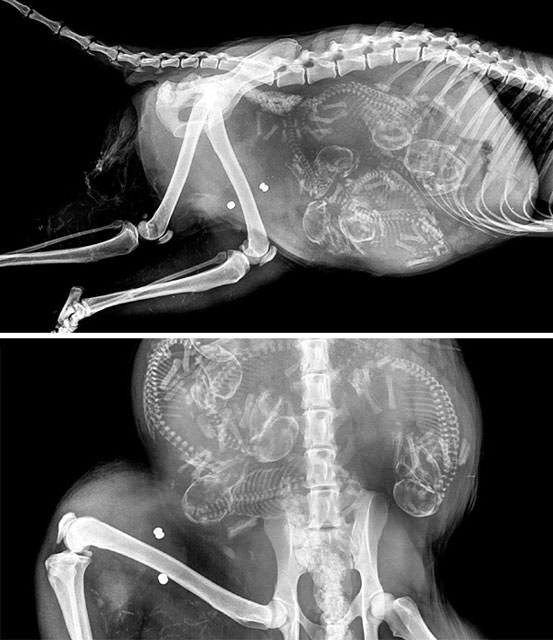

İnsanların ultrason görüntülerini görmeye hepimiz alışkınız. Ancak hamile hayvanların ultrason görüntüleri sizleri çok şaşırtacak.Kaplumbağa

İnsanların ultrason görüntülerini görmeye hepimiz alışkınız. Ancak hamile hayvanların ultrason görüntüleri sizleri çok şaşırtacak.